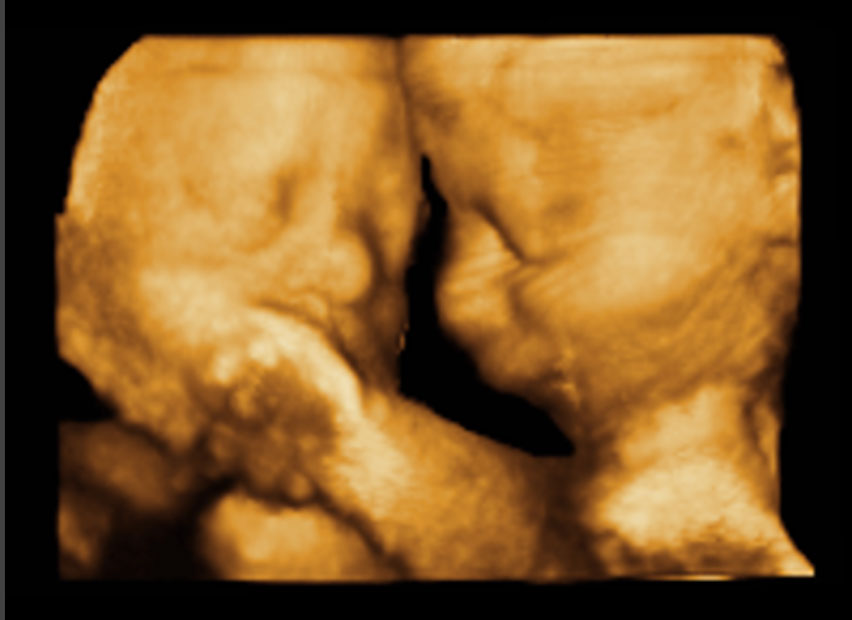

Fig. 12

In questa immagine, i volti di due gemelli all'ecografia 3D eseguita a 28 settimane. L'esame tridimensionale, se eseguito a quest'epoca, quando possibile, permette di evidenziare le caratteristiche del volto fetale, dal momento che la componente di grasso inizia ad essere adeguata. Eseguita al momento dell'esame del secondo trimestre, l'ecografia 3D è meno piacevole perchè il grasso non si è ancora accumulato in misura adeguata, e di conseguenza il volto fetale appare "affilato".